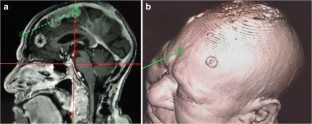

A 68-year-old man in good general health presented with a parasagittal meningioma that recurred following subtotal removal and adjuvant fractionated stereotactic radiosurgery (FSR). The scalp above the tumor location was very diseased and precluded a regular craniotomy for tumor removal. A 4-cm craniotomy was made in the midline forehead, where the skin was normal. A rigid endoscope was advanced under neuronavigation through the interhemispheric fissure, which provided good access with limited retraction, until the tumor was encountered at a depth of 7–8 cm. Two surgeons performed the surgery using a “four-hands technique”. The tumor was removed and the insertion area was resected and coagulated.

Fig. 1